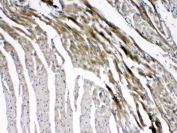

IHC testing of FFPE mouse heart tissue with GJC1 antibody at 1ug/ml. Required HIER: steam section in pH6 citrate buffer for 20 min and allow to cool prior to testing.